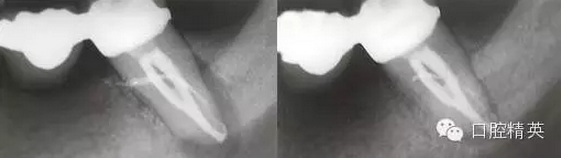

病例2 修復(fù)后根尖出現(xiàn)炎癥冠上開孔再治療

修復(fù)后出現(xiàn)根尖周炎 去除原根充物后試主尖

熱牙膠充填后 一年后復(fù)查病變愈合